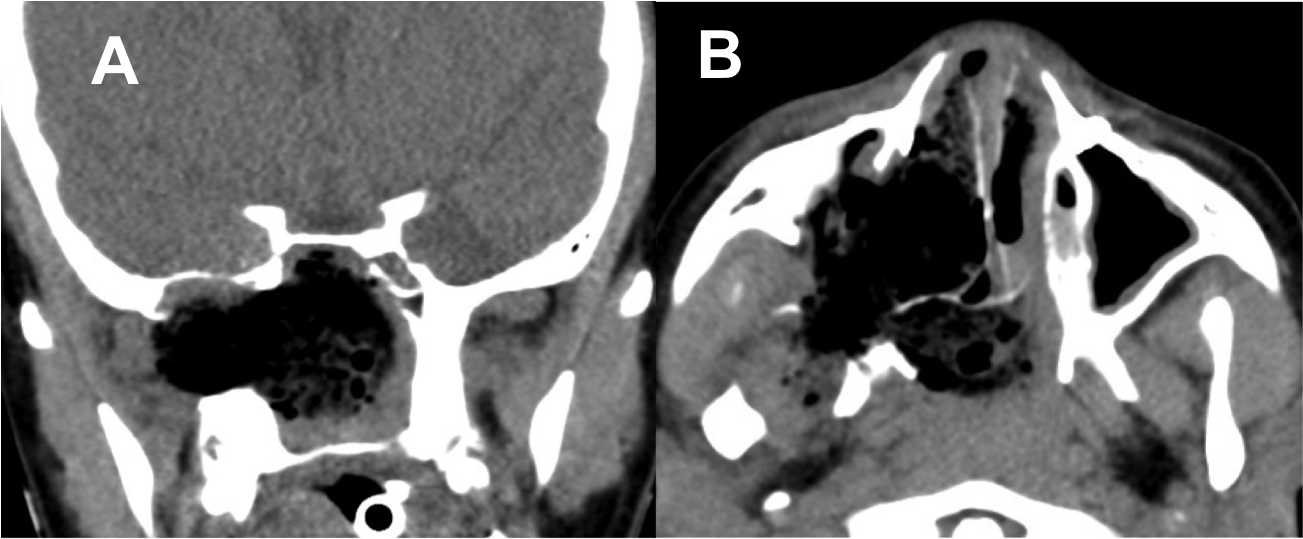

Resultados: Fueron intervenidos 8 pacientes entre los 2 y 14 años, con una edad promedio de nueve años y un seguimiento promedio de 16 meses. En el 75% se hizo una resección total del tumor. Un paciente requirió una reintervención y un paciente fue sometido a radiocirugía post-operatoria. 1 paciente falleció a pesar de múltiples intervenciones, quimioterapia y radioterapia.